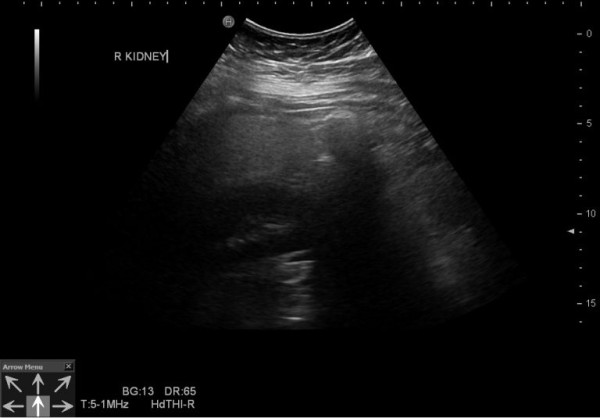

台灣初日診所兒童內分泌暨減重專科醫生王律婷分享案例,指一名年僅13歲的青少年,身高160cm、體重72kg,竟已出現中度脂肪肝。從檢查結果顯示,少年的肝功能指數(ALT)已飆升至72 U/L(正常值約45以下),而三酸甘油酯則為160 mg/dL,同時也出現胰島素阻抗的現象。